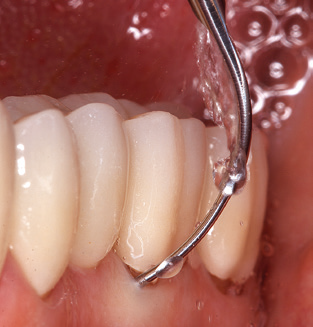

The current working concept for SPT

Updating the patient’s medical history is an important aspect of SPT and should occur at least once per year. It helps the dental team to identify and document any new risk factors. Especially when a patient is treated over many years, it is important to establish whether patient-specific and general health risk factors have changed. This primarily concerns a heightened risk as a result of diabetes, but other general conditions (cardiovascular disease and neoplasia) can also produce a modified risk profile as a result of the treatment performed and medication administered. Accordingly, updating the medical history as part of SPT is very important, as a modified risk profile may trigger the need to adapt the treatment interval. In the next step, it is important to afford the diagnostics due attention. Whilst instruments are a central aspect of SPT, findings and their documentation must never be neglected. The periodontological findings are essential for a good diagnosis; increases in the pocket depths and the BOP index are clear indicators of advancing periodontal and peri-implant disease. As such, the team should not shy away from probing implants too, with the aim of gathering the requisite data. At the same time, it is important to use periodontal probes with millimetre markings. Metallic probes have already been used for determining pocket depths around natural teeth for decades. In the case of implants, the challenge of recording correct and reproducible pockets depths is even greater. As the discrepancy between the implant diameter and the contour of the superstructure regularly results in overcontouring of the superstructure, flexible probes which still feature millimetre markings are a sensible solution for measuring pocket depths around implants (e.g., Colorvue Kit PCV11KIT6, HuFriedy; Fig. 4).